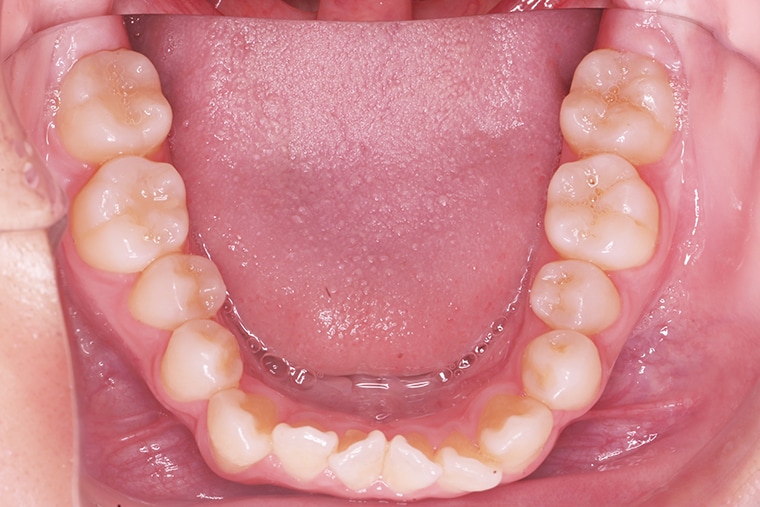

20歳男性ガタガタな歯のマウスピース矯正-矯正期間9ヶ月

- 治療費用

- 880,000円(税込)

- 治療期間

- 9ヶ月

- 性別

- 男性

- 年齢

- 20歳

- 抜歯

- 無し

- 治療方法

- マウスピース矯正(インビザラインModerate)による治療方法

- 治療リスク

- 1日22時間の装着時間を守らないと治療期間が遅くなり、歯並びの質が悪くなります

上下のガタつきがずっと気になっていて、朝鏡を見るときにいい気分にはなれませんでした。

ワイヤー矯正は痛いイメージがあったのと、治療期間が長くかかるイメージもあったため、なかなか踏み切れずにいました。

そこでマウスピース矯正を選んだのですが、実際に始めてみると、想像していたよりも負担が少なく、期間も短く済むことが分かりました。装置を交換した2、3日だけ少し違和感や軽い痛みがありましたが、日常生活に大きな支障はなく、普段の生活や食事にもほとんど影響がありませんでした。

治療を始めてから少しずつ歯並びが整っていくのを目で確認できるのは励みになり、モチベーションを保つことができました。毎日の装着や歯磨きの習慣も自然と身につき、歯への意識も以前より高まりました。

約9ヶ月の治療を経て、上下のガタガタだった歯はきれいに整い、朝鏡を見ることが苦にならなくなりました。今では口元を隠す必要もなくなり、笑顔に自信が持てるようになりました。思っていたよりも短期間で、そして痛みもほとんどなく変化を実感できたことが本当に嬉しいです